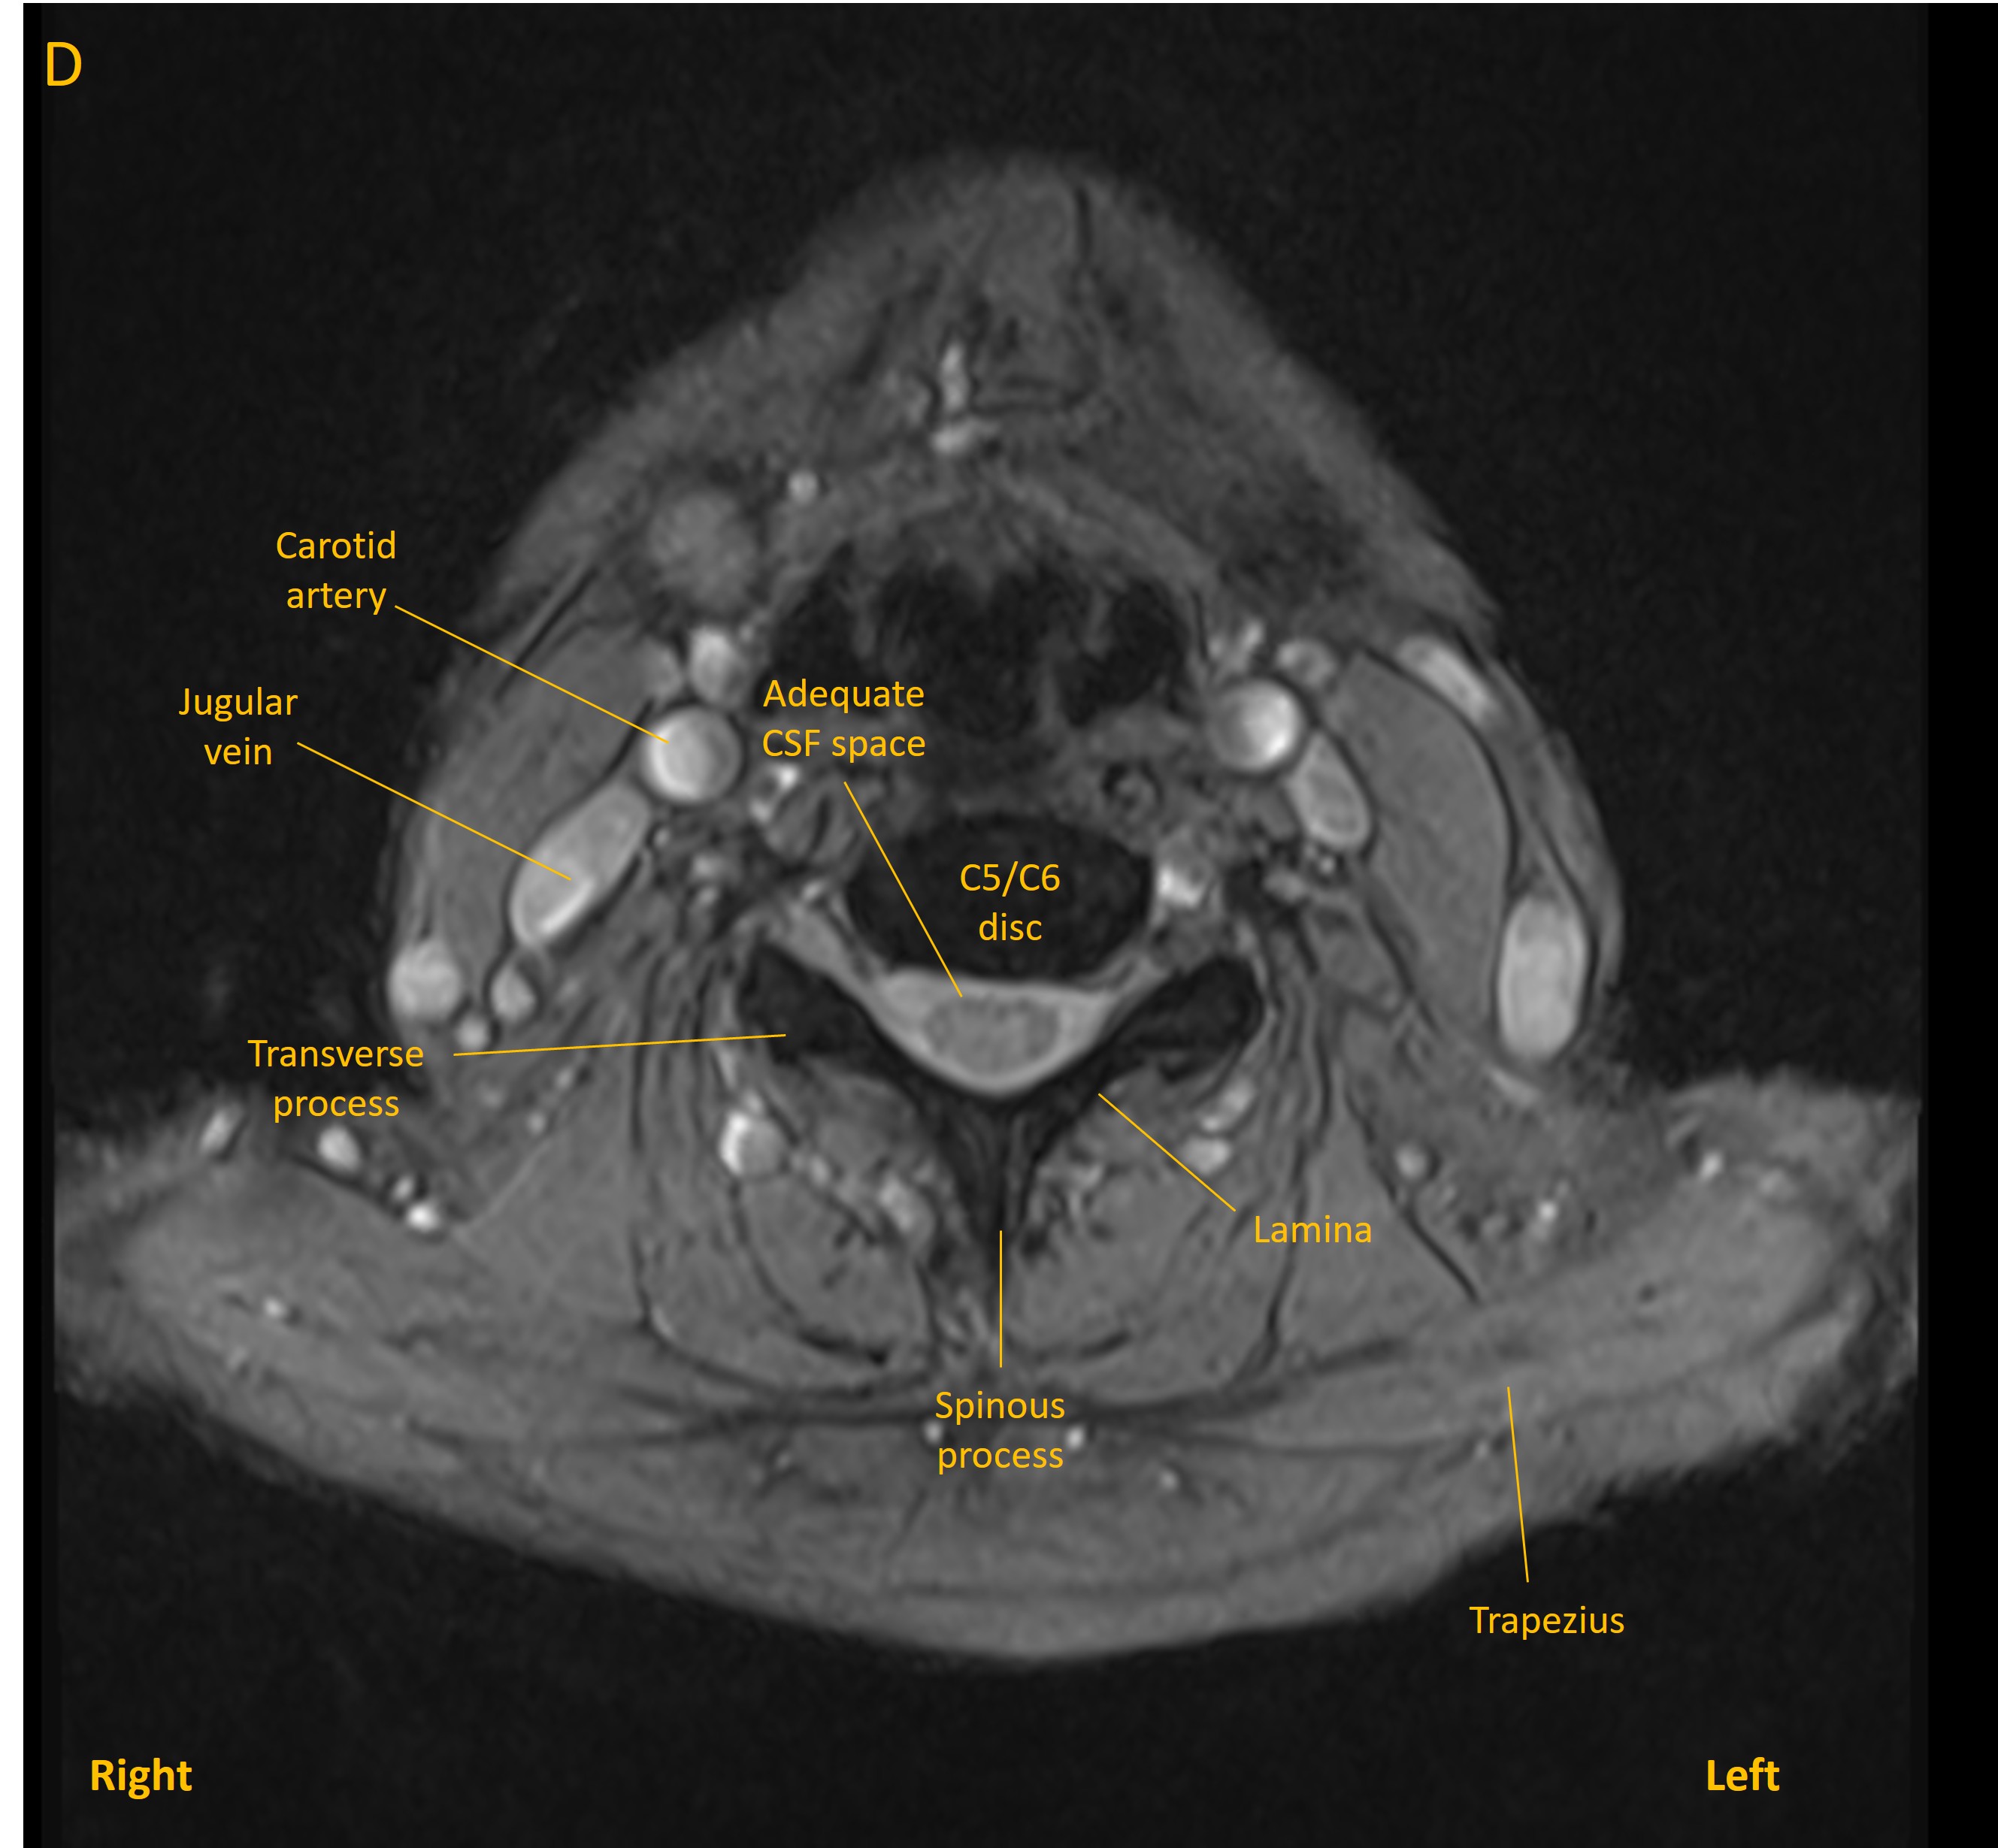

Degenerative changes were seen at multiple levels in the cervical spine, as is frequent at this age, and with some levels featuring mild narrowing of exit foramina and contact with nerve roots. These were evident at levels C3/C4 (B), C4/C5 (C) and C5/C6(D) - although none of these were clinically evident. Disc bulges at other levels did not compress the cord.

Axial MRI